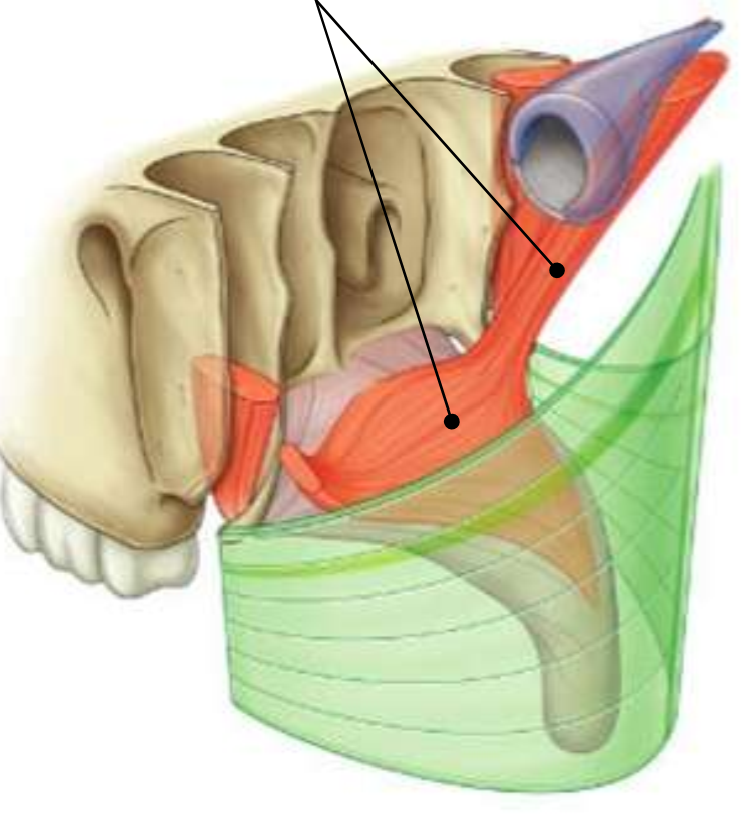

What muscle is this?

superior constrictor

What is the upper border of this muscle?

palatopharyngeal sphincter

What is 1?

pterygomandibular raphe

What is 2?

stylohyoid ligament

What are the attachments of this muscle?

pterygoid hamulus, pterygomandibular raphe, posterior end of mylohyoid line → pharyngeal raphe